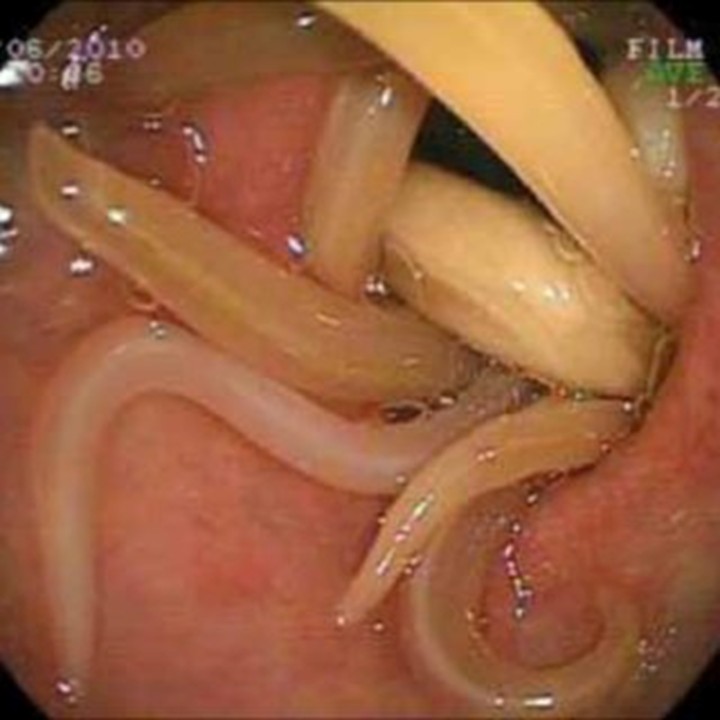

Paciente femenina de 4 años

quien es llevada de emergencia al hospital por dolor abdominal difuso. Al

examen físico se encuentra una infante con la circunferencia abdominal

aumentada, sin ruidos peristálticos, dolor a la palpación, timpanismo aumentado

y sensación de masa a nivel intestinal. Se decide realizar una endoscopía que

demuestra lo de la siguiente fotografía:

¿Cuál es el nombre del medicamento

indicado que causa parálisis espástica y además tiene pocos efectos

secundarios?